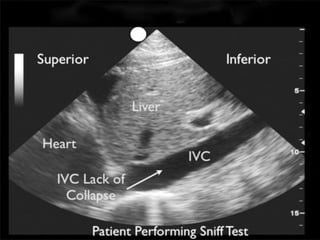

IVC Ultrasound

3 cm

Spontaneously breathing patient - 40-50% collapse

3 cm Spontaneously breathingpatient - 40-50% collapse